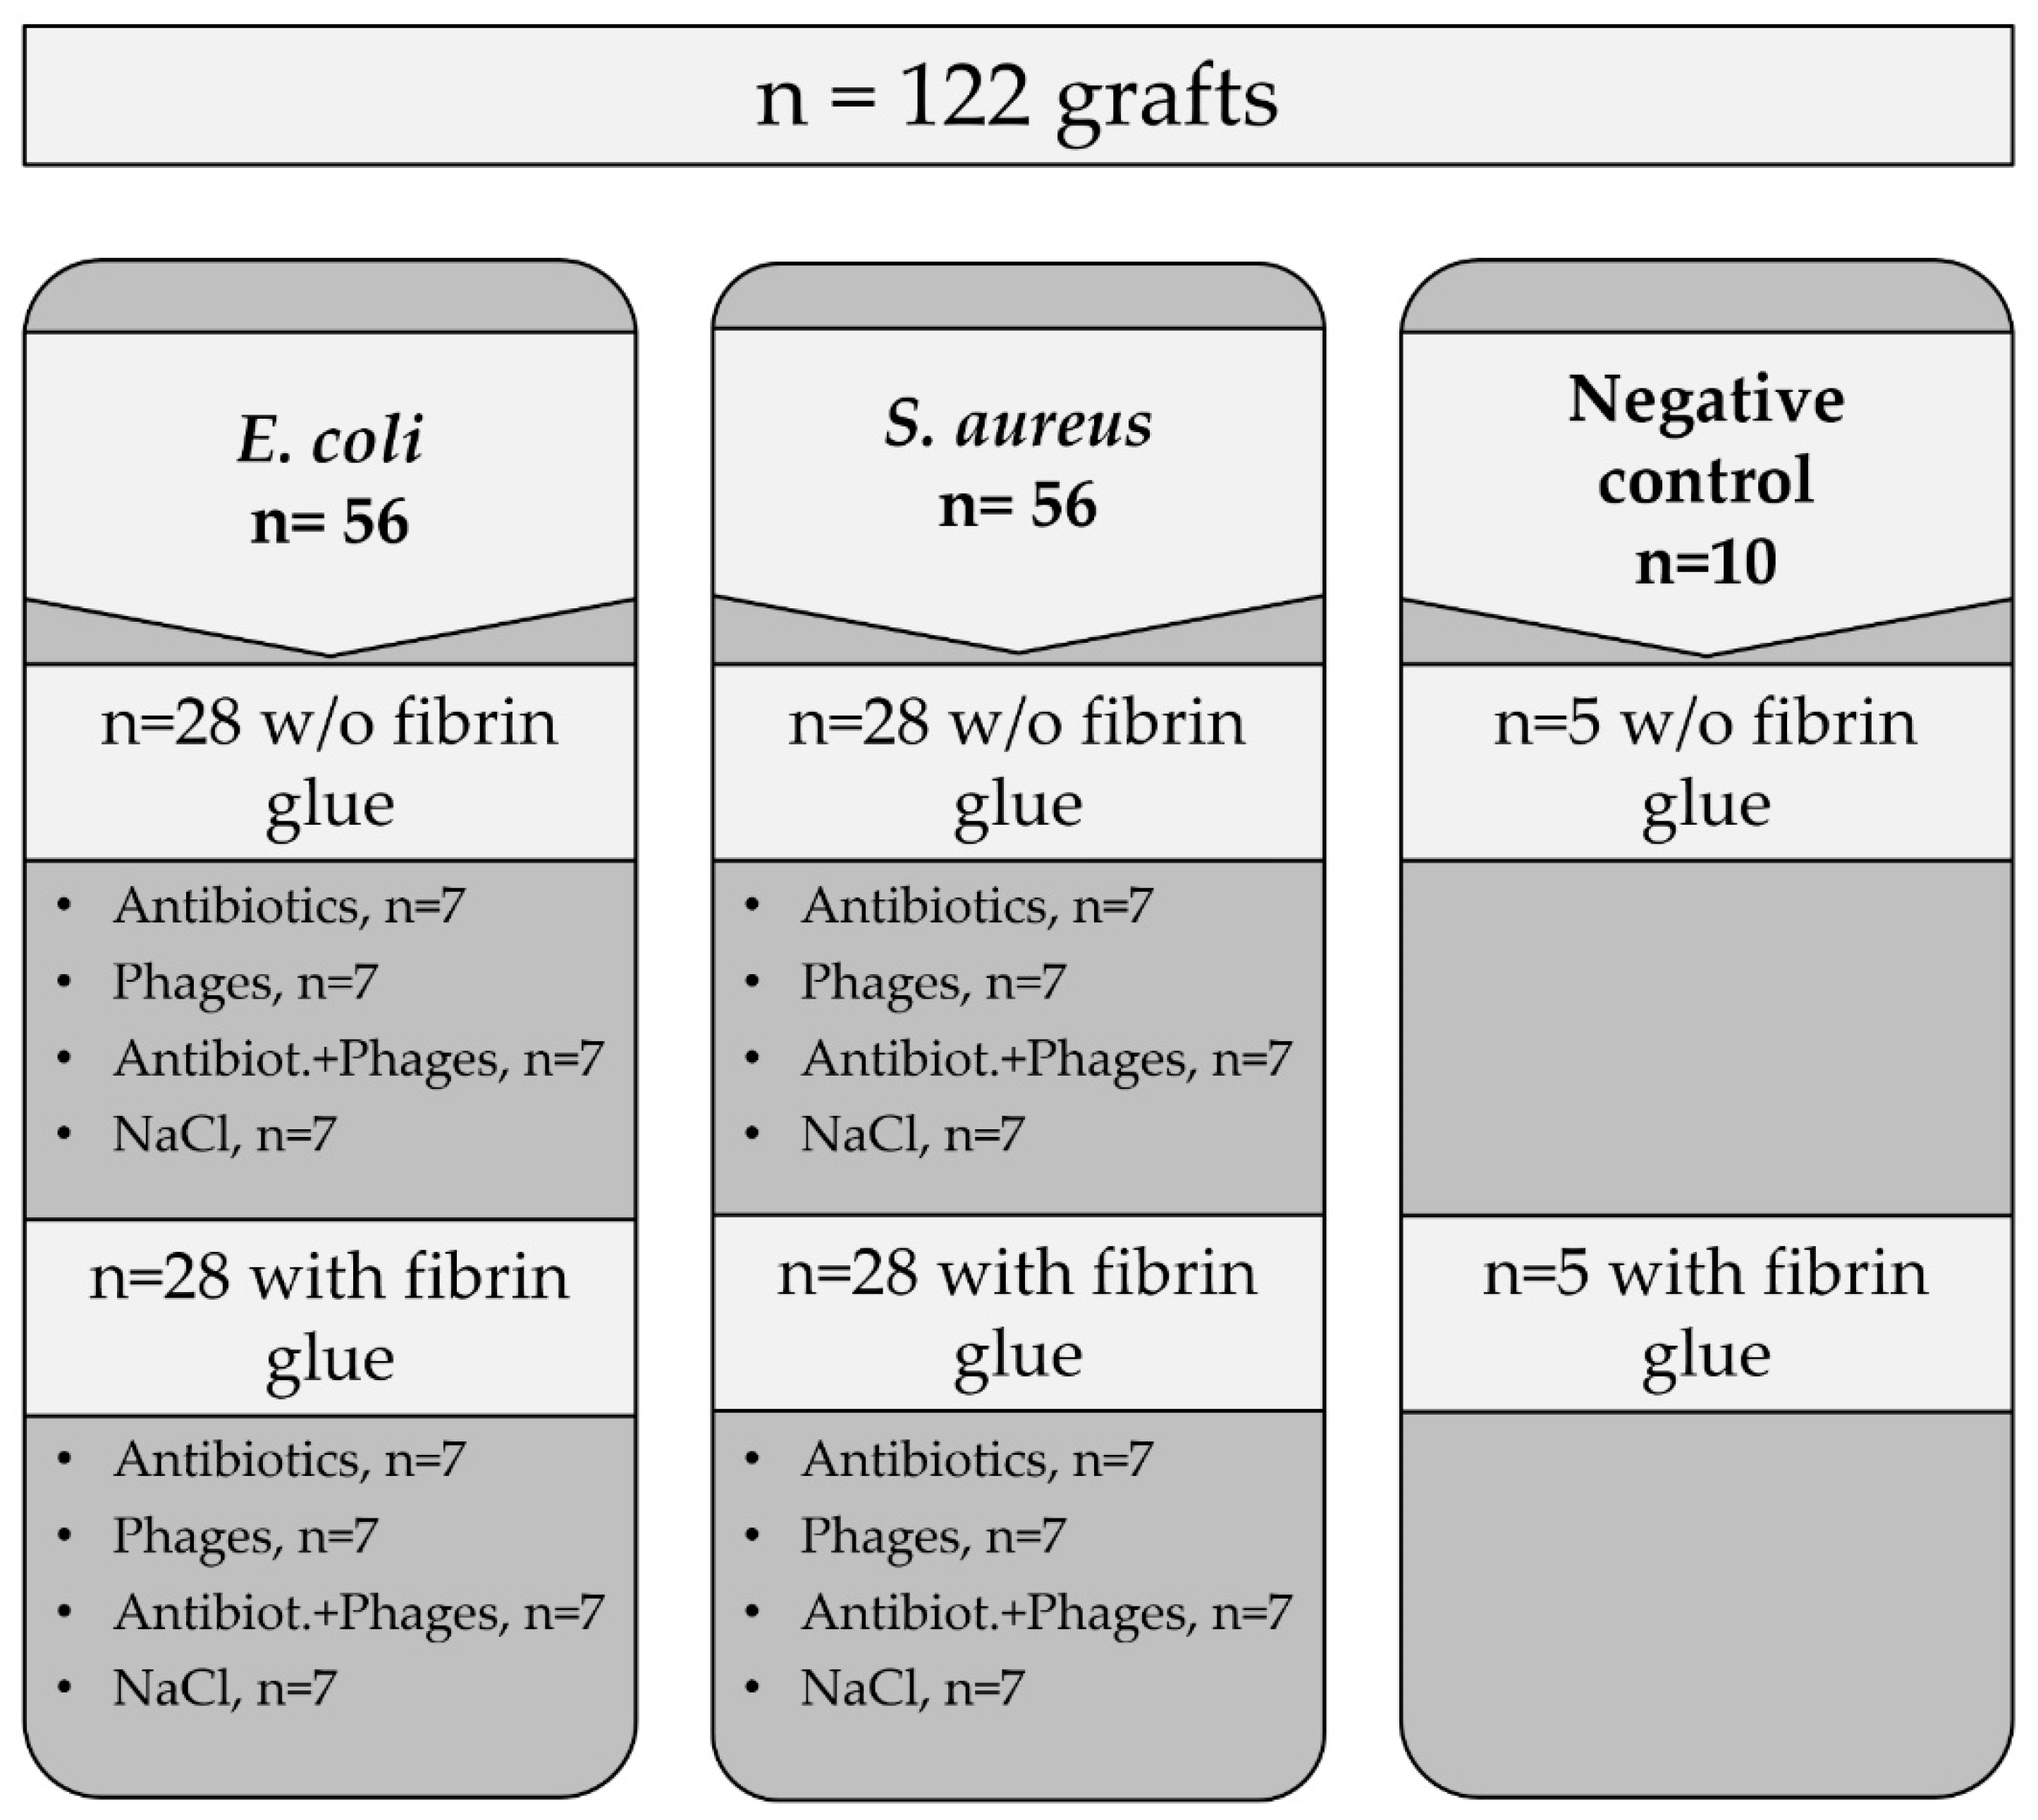

4. Materials and Methods

4.2. Methods

4.2.4. Processing of Samples—Antibacterial Activity against Single Contamination

4.2.6. Processing of Samples—Antibacterial Activity against Recurrent Contamination